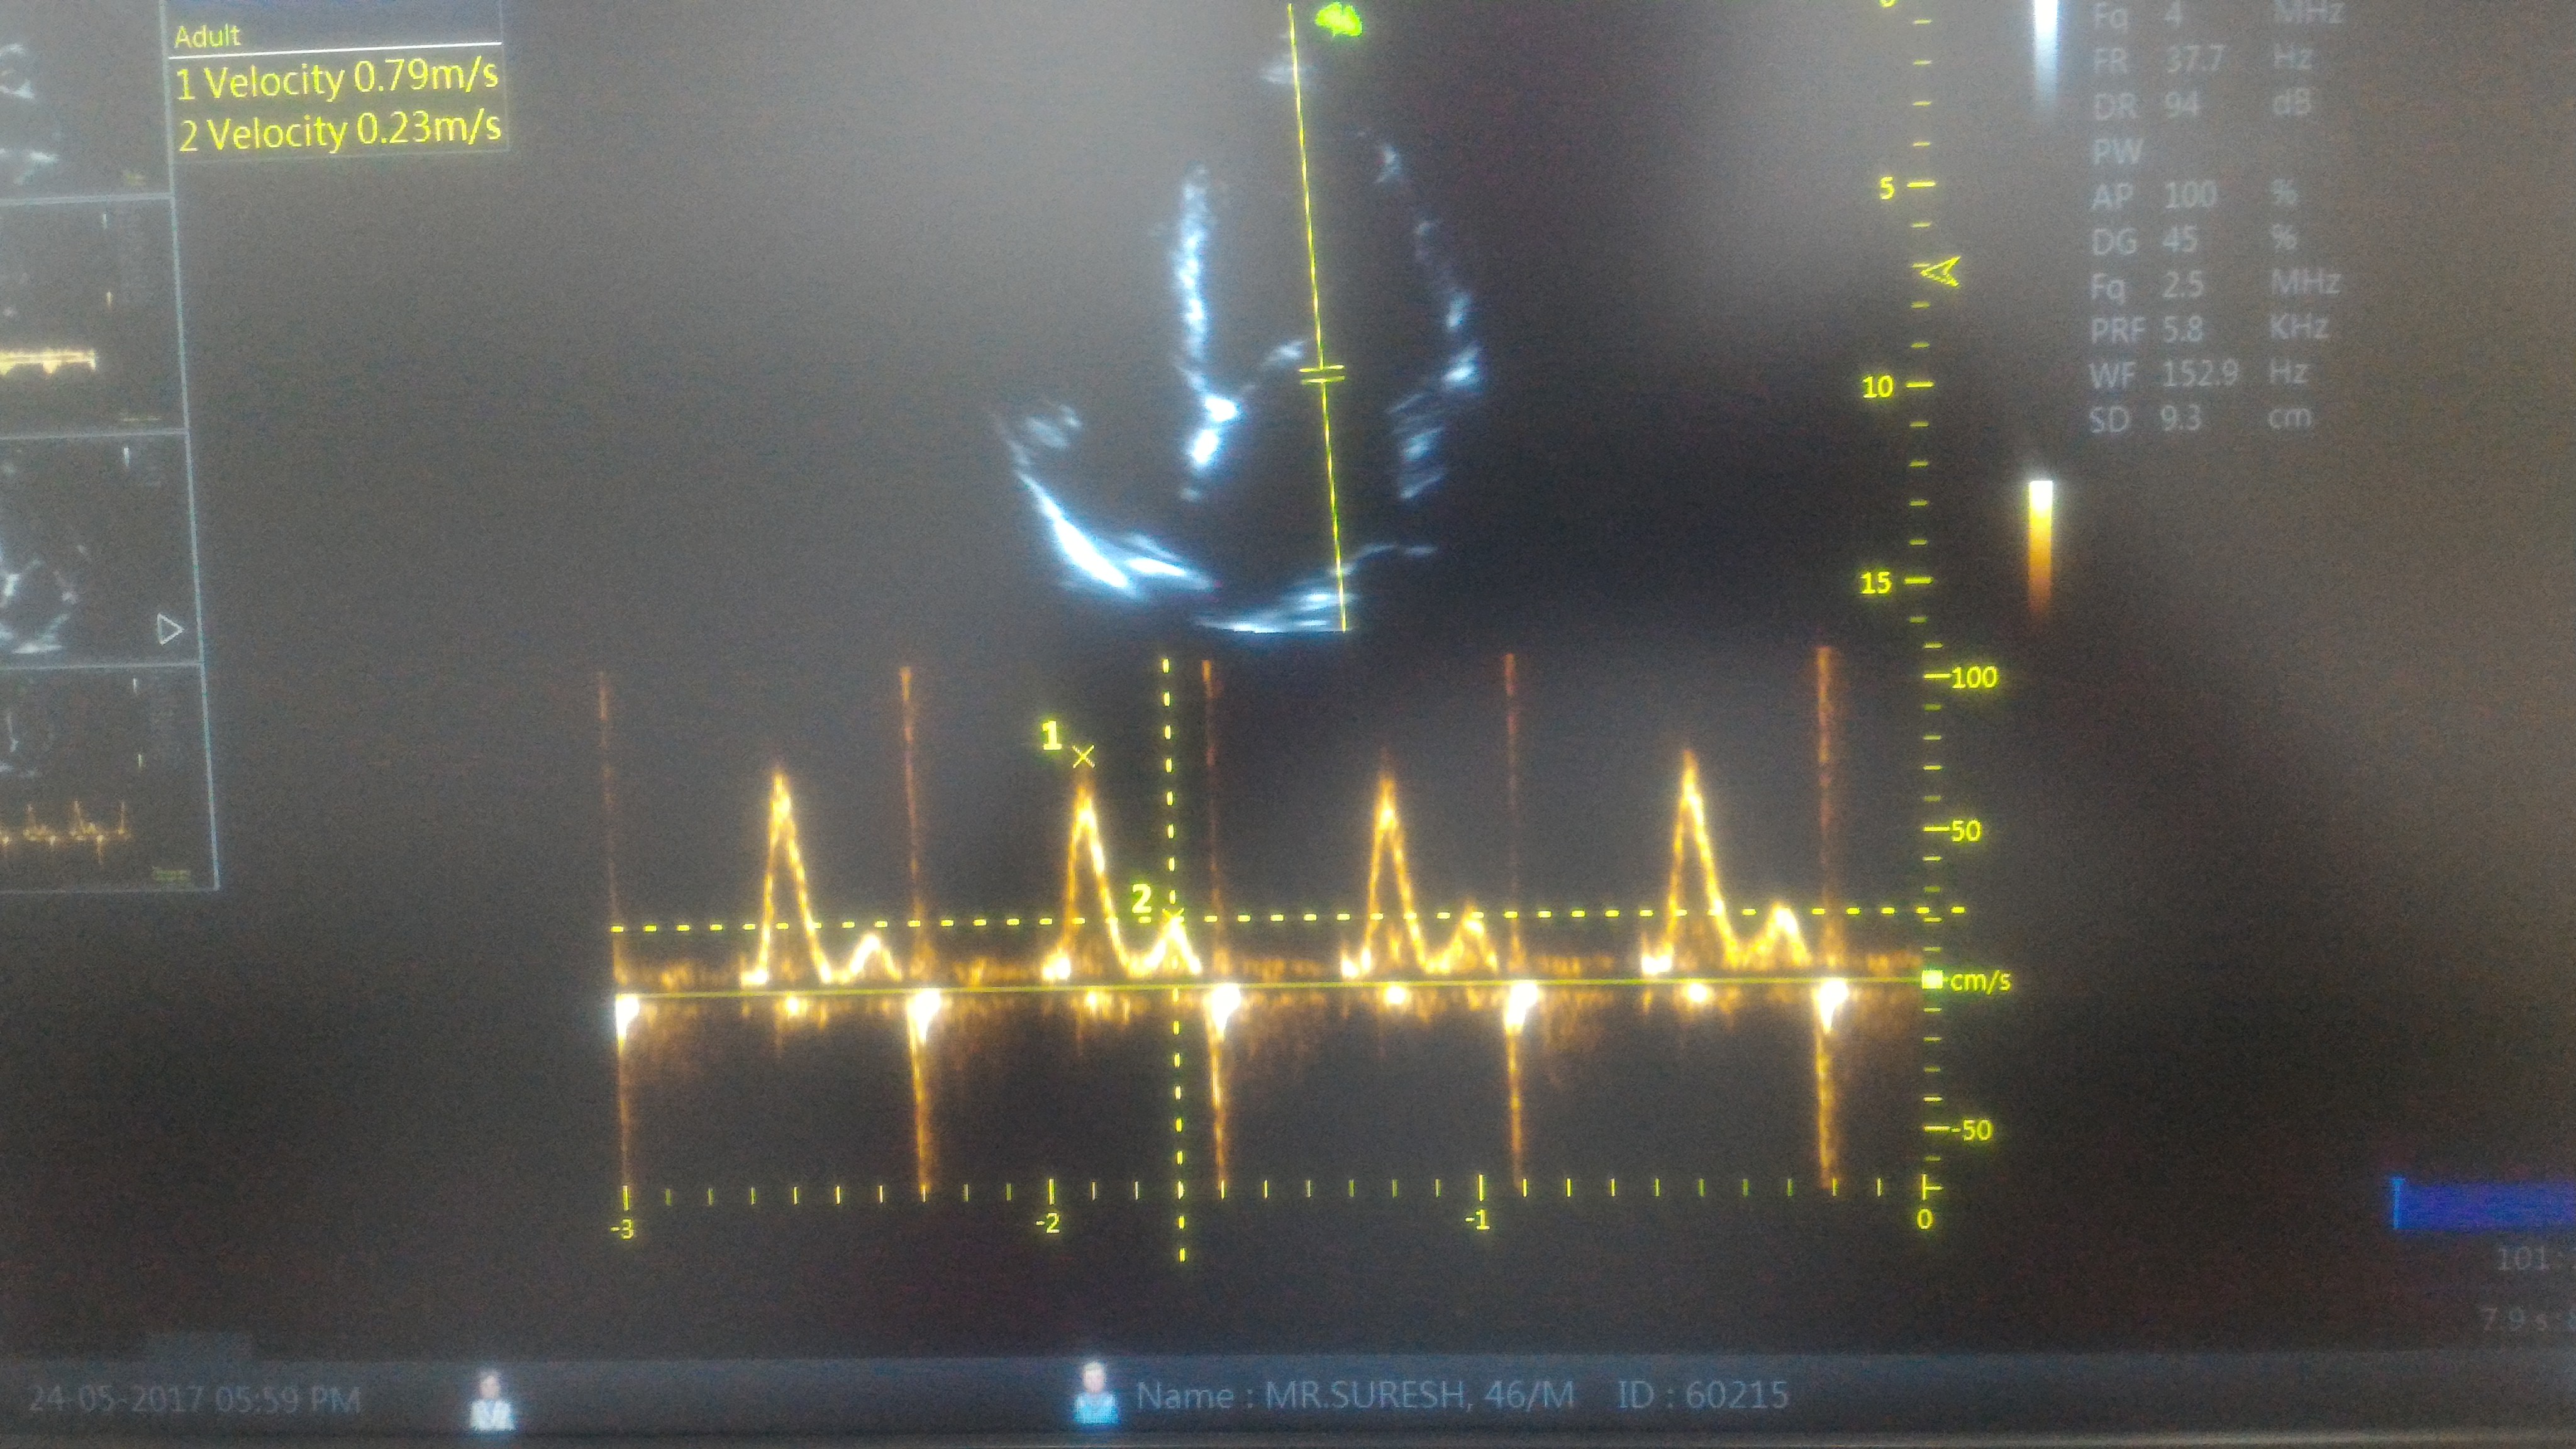

We don’t require complex tissue Doppler parameters to diagnose high-grade LV diastolic function.Just have a look at LA dimension, concentrate the E to A ratio. A tall E that humbles the A by more than 2 to 3 times is clear evidence for LA mean Pressure exceed 18 to 20 mmhg or so.

This , in combination with dilated LA is a marker of chronic severe diastolic dysfunction.The fact that A is diminutive in no way takes the Importance of Atrial contribution to LV filing at this critically compromised LV status.

Note E:A ratio is 3:1 .This simply means the early (and mid to a certain extent ) diastolic pressure in LA is high and most of the filling takes place before Atrial contraction .There is one more reason for diminutive A . Atrial contractility fails to prevail over E in late diastole as LV end diastolic pressure is significantly high in these patients with diastolic dysfunction.

Relying on E:A ratio to diagnose diastolic dysfunction may appear amateurish for some of us .The rampant reporting of E>A for grade 1 diastolic dysfunction has made this parameter a “Doppler cliché”. But , the fact of the matter is, it does help us confirm severe (Grade 4) diastolic dysfunction when E stands tall and towering over an almost dwarfed A.